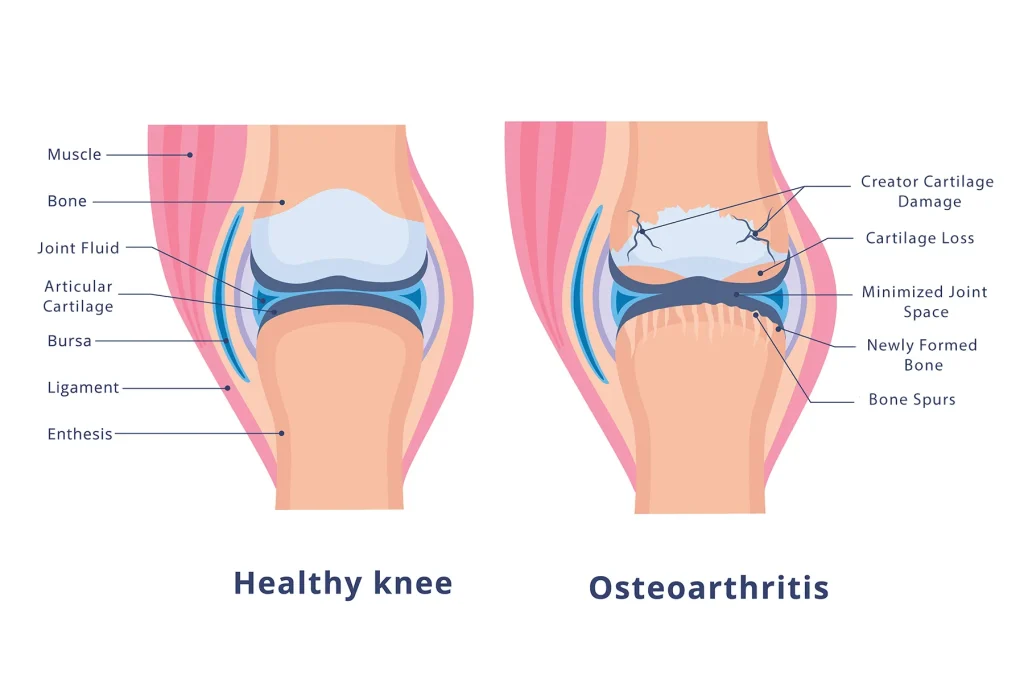

Knee arthritis is a condition where the cartilage in the knee joint gradually wears away, leading to pain, stiffness, swelling, and reduced mobility. It can affect one or both knees and is more common in older adults, though younger people can develop it due to injury or genetic factors.

These factors can lead to inflammation, breakdown of cartilage, and changes in the underlying bone.

- X-rays to detect joint space narrowing, bone spurs, or changes in bone structure